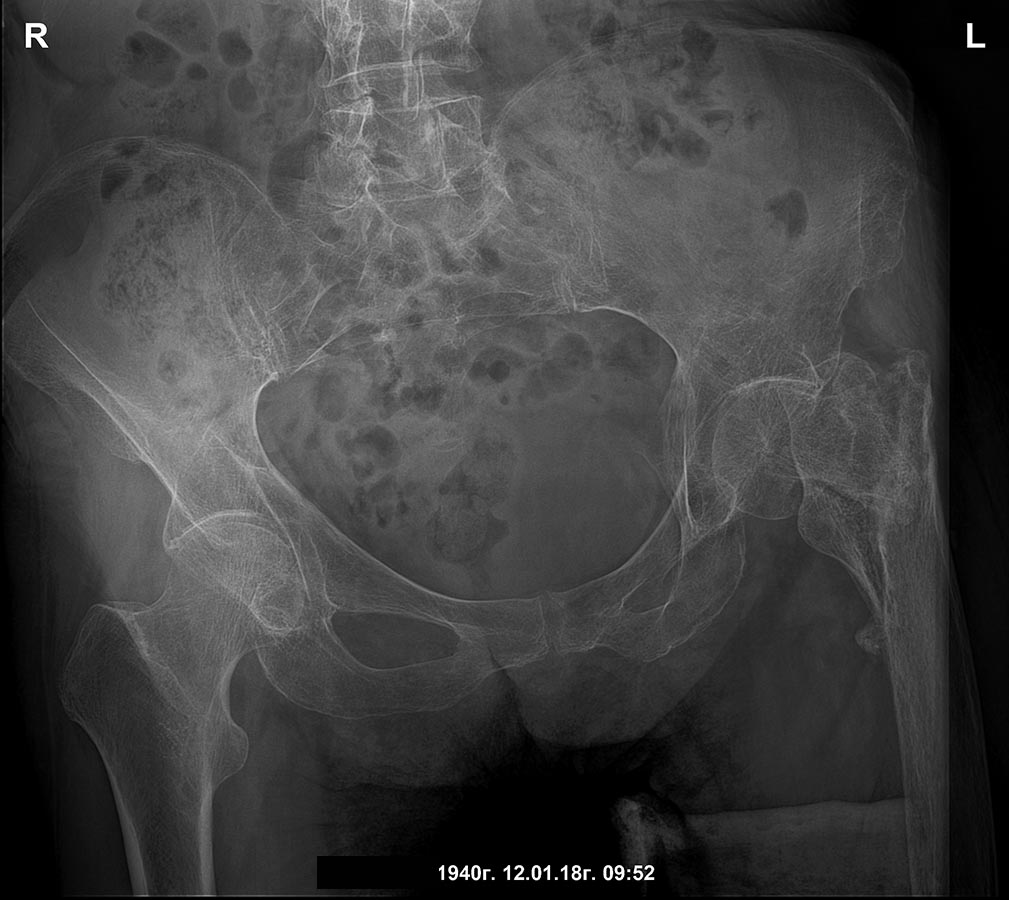

[Ortho] Сросшийся чрезвертельный и перелом н\3 бедра

боковая